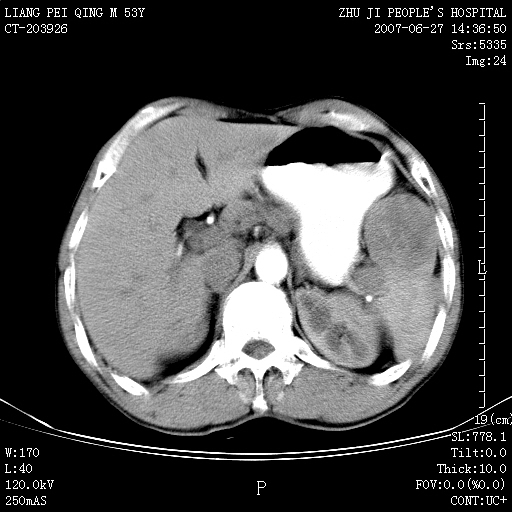

以下是引用余辉在2007-6-27 18:46:00的发言:[br]病灶多发,内可见大片状低密度区,病灶病灶等密度区轻度强化,动脉期后期病灶低密度区与高密度区对度增加,考虑1淋巴瘤2转移瘤3血管内皮细胞瘤(不知有否静脉期及延迟期扫描)

以下是引用zzzzhhhhaaaannnn在2007-6-27 20:44:00的发言:[br]脾脏 肋骨转移可能性大,下腔静脉内有癌栓

以下是引用狙击手在2007-6-28 10:35:00的发言:[br]1:定位:来源于脾脏。2:强化:强化,但不均匀。3:下腔静脉癌栓?下腔静脉充填不均匀与增强时间有关,延时即可明确。4:肋骨破坏?看起来并不确切。综上考虑几个最常见诊断:1;淋巴管瘤;2;血管内皮肉瘤(高度恶性,早期即可转移,常见肝,肺,骨)3;转移瘤(无特征性,只有肝或其它腹腔脏器有类似病变时,才可提示之)